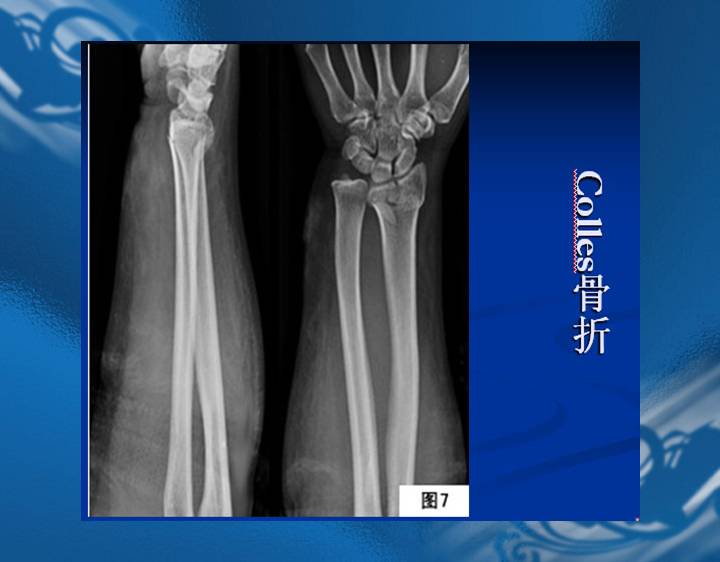

执业医师资格考试“实践技能”影像学辅导资料